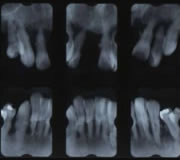

歯周ポケットの深さが3~6mm以内、歯のグラグラ揺れる幅が1~2度(1.0mm~2.0mm)以内のもの。X線写真を撮ってみると、歯槽骨の吸収が歯根の長さの3分の1から3分の2に収まっているものです。

歯肉は腫れていて、歯と歯肉の境目にはプラークや歯石が目立ちます。そのため歯肉は出血しやすく、歯周ポケットから膿みがでることが見受けられます。レントゲン写真では、歯を支えている骨が減ってきていることがわかります。 |